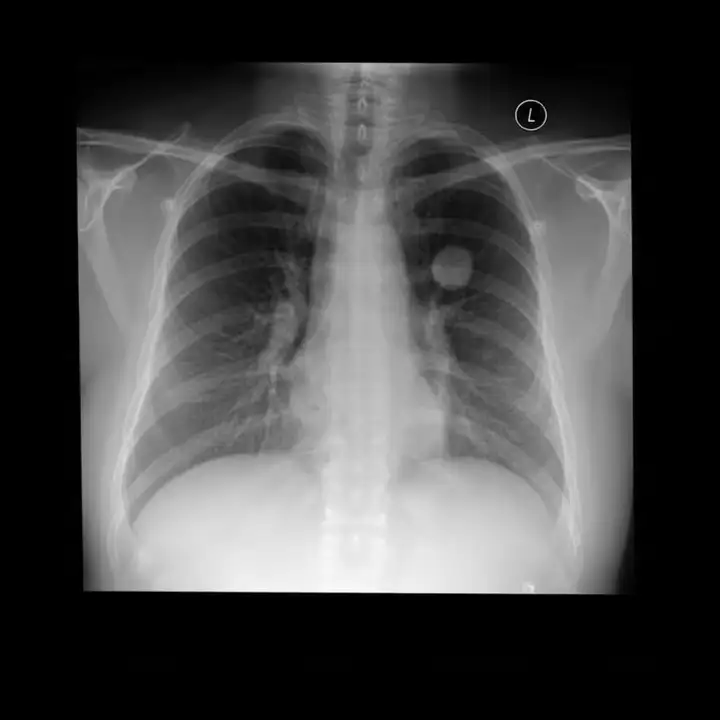

Med-Banana-50K 是一个面向文本引导医学影像编辑任务的大规模数据集,旨在支持多模态模型在不同医学影像模态与疾病条件下的病灶编辑能力研究。数据集包含超过 50,000 条医学影像编辑样本,并额外提供约 37,000 条失败编辑尝试及其完整评估日志,覆盖胸部 X 光、脑部 MRI 与眼底影像三种模态以及 23 种疾病类型。所有样本均支持病灶添加与去除两种编辑方向,并附带基于自动评估流程生成的多维质量判定结果,适合用于医学图像编辑、模型评测与误差分析研究。